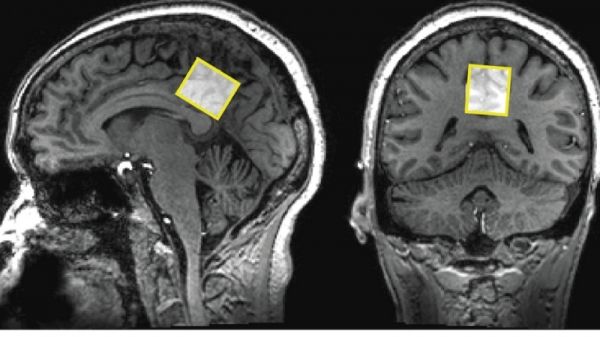

Using strong and targeted but noninvasive magnets at specific sites in the brains of people with and without mild learning and memory problems, Johns Hopkins researchers report they were able to detect differences in the concentrations of brain chemicals that transmit messages between neurons. The strength of these magnetic fields allows the researchers to measure tiny amounts and compare multiple brain metabolite levels at the same time. These studies may ultimately help to reveal what initiates memory decline and may, perhaps, even predict dementia risk.

Image Credit: Johns Hopkins Medicine